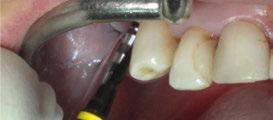

-Registros fotográficos intra y extraorales (Figura 1 a-c).

Figura 1a. Foto intraoral frontal inicial.

Figura 1b. Foto intraoral lateral izquierda inicial.

Figura 1c. Foto intraoral lateral derecha inicial.